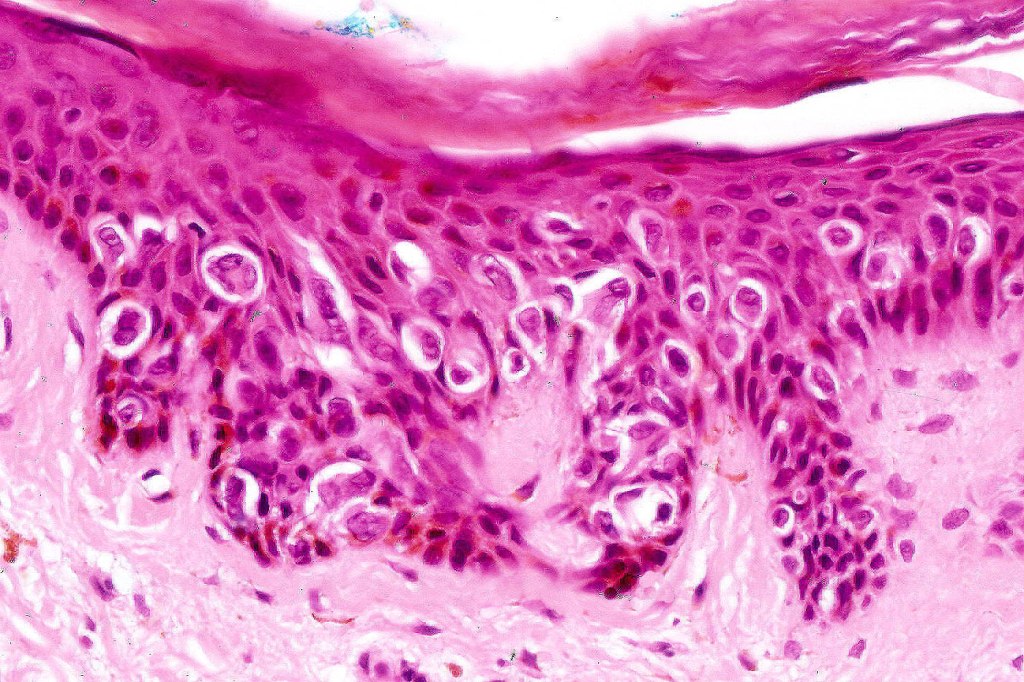

•Intraepidermal proliferation of epithelioid Pagetoid cells with plentiful eosinophilic cytoplasm & vesicular nuclei with conspicuous eosinophilic cytoplasm

.Retraction artifact

Pagetoid Spitz nevus may be confused with superficial spreading melanoma. The strikingly uniform Spitz population with retraction artifact, absence of pleomorphism and mitotic activity should make the distinction easy. Unfortunately insufficient immunohisyochemistry literature is available.